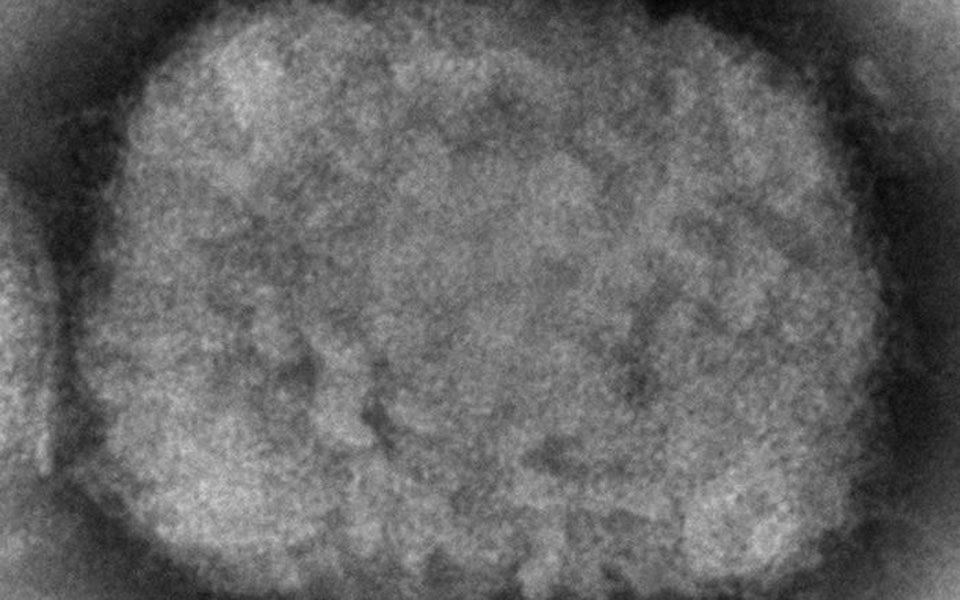

Μόσιαλος για κρούσμα ευλογιάς των πιθήκων: «Ο κίνδυνος για τον γενικό πληθυσμό παραμένει ελάχιστος»

Έξι σημεία που πρέπει να θυμόμαστε για την ευλογία των πιθήκων αναφέρει ο Ηλίας Μόσιαλος μετά την ανακοίνωση του πρώτου κρούσματος στην Ελλάδα.

Μόσιαλος για ευλογιά των πιθήκων: Υπάρχουν και θεραπείες και εμβόλια

«Στην Ελλάδα, μέχρι στιγμής, δεν υπάρχει κρούσμα. Ας θυμόμαστε πως δεν βοηθά ούτε ο στιγματισμός, ούτε ο πανικός, ούτε η τρομολαγνεία. Ας μείνουμε ενημερωμένοι και ας προσέχουμε» ανέφερε ο κ. Μόσιαλος.

Μόσιαλος για ευλογιά των πιθήκων: Να μην στιγματίζουμε τους ασθενείς, δεν είναι σεξουαλικά μεταδιδόμενη νόσος

«Δυστυχώς, ήταν ατυχής η αναφορά από δημόσια στόματα πως οι ασθενείς με ευλογιά στην πλειονότητά τους ήταν άντρες που συνευρίσκονται ερωτικά με άντρες» επεσήμανε ο καθηγητής Πολιτικής της Υγείας της Σχολής Οικονομικών & Πολιτικών Επιστημών.